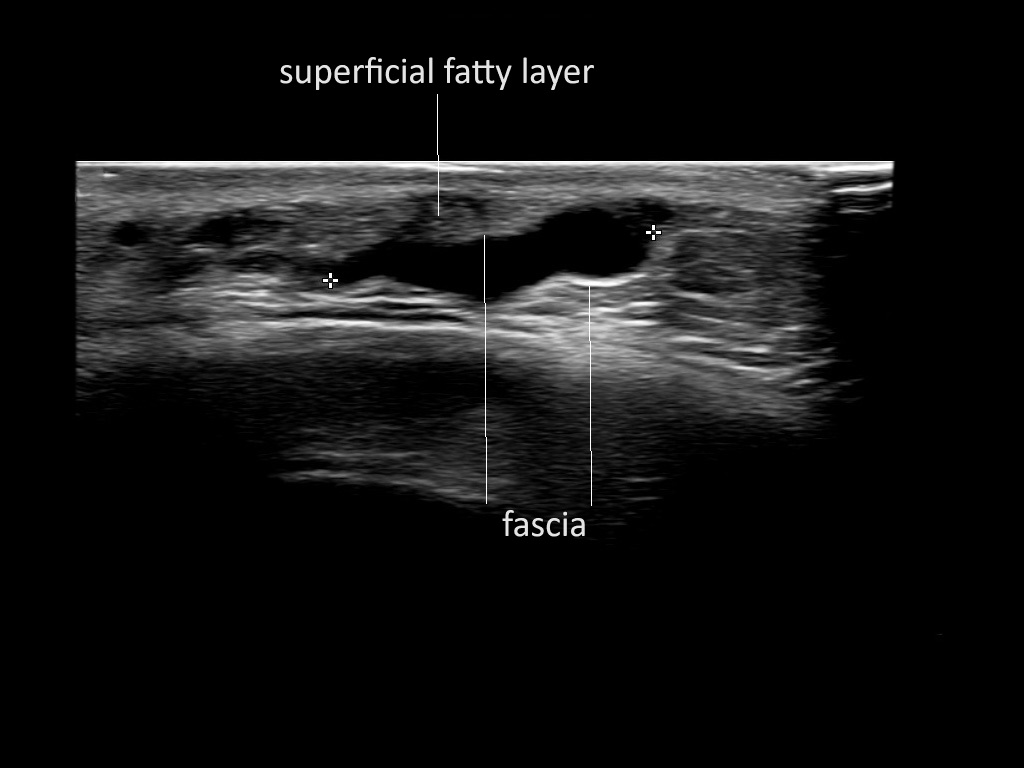

Fascia

Filler deposits may end up unintentionally in the SMAS or fascial layers of the skin. Very often this will not lead to adverse events, however, adverse events ( nodules, migration / redistribution impaired muscle movement and smiling and malar edema) are are often related to filler ending up in the SMAS or fascia.

Study the first image to recognize the different layers. If you are sure about the layers, swipe to the second image to view the answer (if applicable).